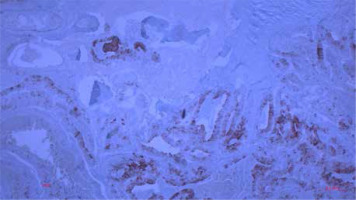

Figure 7

Histological finding of metastatic CRC in the tibia with positive immunohistochemical reaction to CK8 (100×)